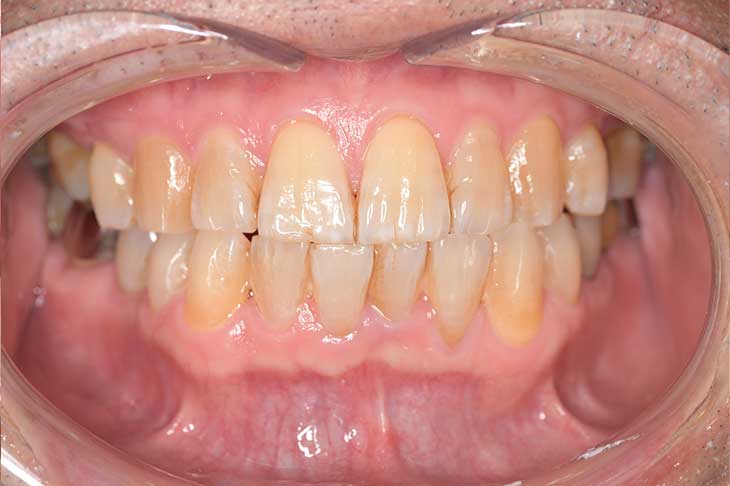

Before

After

基本情報

| 主訴 | 見た目をきれいにしたい |

| 治療期間 | 6ヶ月 |

| 治療費 | ジルコニアボンド(セラミックの被せもの)¥165,000×7(税込み) オフィスホワイトニング4回 ¥4,400×4(税込み) ホームホワイトニング¥11,000 |

| リスク・副作用 | かみ合わせがとても強い方の場合、稀に割れてしまうことがあります。 |

| 先生からの提案 | 上の前歯6本と右下の2番目の歯はセラミックの被せもので治療。 残りの下の前歯5本はプラスチックの材料で虫歯を治療し、 ホワイトニングをおこないました。白くなったご自身の歯の色に合わせてセラミックの 被せものを作成しています。 模型上で完成後をシュミレーションし、上の歯茎の位置をきれいに見えるように 揃えています。(外科処置はしていません) |